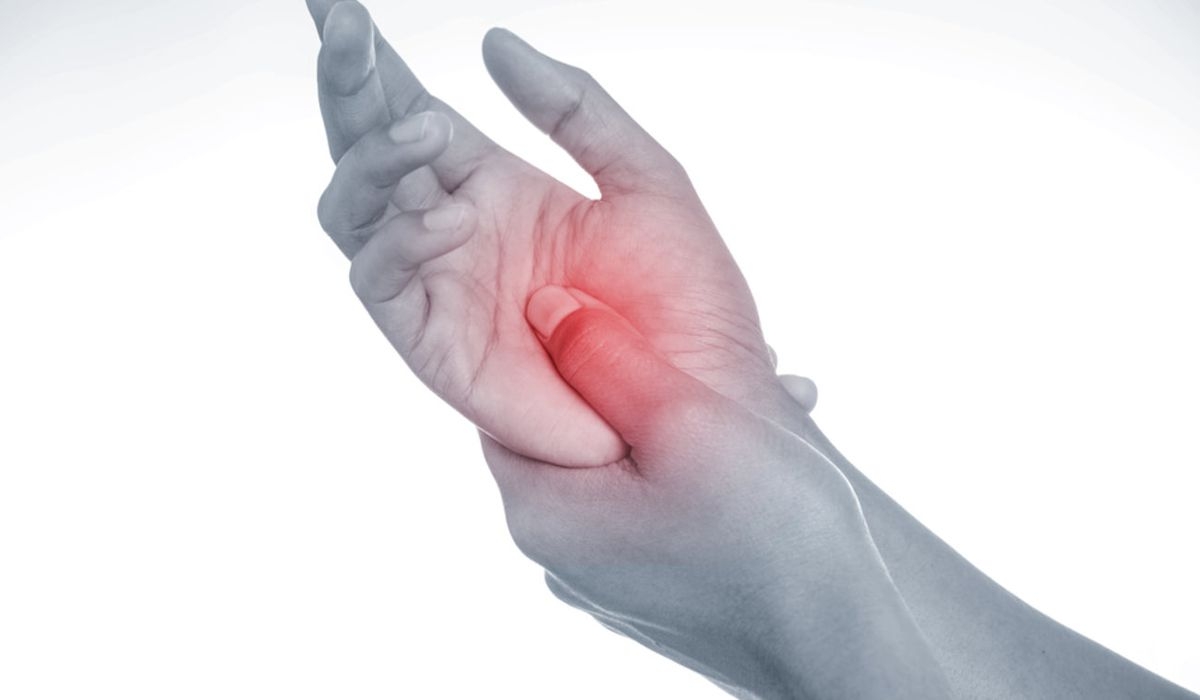

Γνωρίζατε πως τα άτομα που έχουν ρευματοειδή αρθρίτιδα έχουν μερικές περιόδους όπου δεν εμφανίζουν συμπτώματα και άλλες φορές που τα συμπτώματα παρουσιάζουν έξαρση;

Επί του παρόντος, δεν υπάρχει θεραπεία για την ρευματοειδή αρθρίτιδα, αλλά η σωστή θεραπεία και η μέτρια άσκηση μπορούν να βοηθήσουν στην μείωση των φλεγμονών. Εάν η ρευματοειδής αρθρίτιδα αφεθεί χωρίς κατάλληλη αγωγή, οι αρθρώσεις, ο χόνδρος και τα οστά στις πληγείσες περιοχές μπορεί να καταστραφούν.

Ρευματοειδής αρθρίτιδα: Τα πρώιμα συμπτώματα

Τα κύρια συμπτώματα της ΡΑ είναι ο πόνος και η ακαμψία των αρθρώσεων. Πριν εμφανιστούν αυτά τα συμπτώματα, όμως, ο ασθενής μπορεί να παρουσιάσει κάποια πρώιμα σημάδια.

Ορισμένα από αυτά τα σημάδια σχετίζονται με το πώς το άτομο αισθάνεται συνολικά, ενώ άλλα αφορούν ειδικά τις αρθρώσεις. Τα συμπτώματα που επηρεάζουν τις αρθρώσεις ενός ατόμου είναι πιο πιθανό να υποδηλώνουν ΡΑ, ιδιαίτερα εάν επηρεάζουν περισσότερες από μία αρθρώσεις ή και τις δύο πλευρές του σώματος.

Τα σήματα έγκαιρης προειδοποίησης της ΡΑ περιλαμβάνουν:

5. Ευαισθησία αρθρώσεων

Η ρευματοειδής αρθρίτιδα εκδηλώνεται και με αυξημένη ευαισθησία στις αρθρώσεις. Αυτό επηρεάζει τόσο χέρια, όσο και πόδια και θεωρείται τυπικό πρώιμο σημάδι της ΡΑ.

Στα χέρια, η άρθρωση στην μέση και στην βάση των δακτύλων μπορεί να γίνει πιο ευαίσθητη, όταν πιέζεται ή κατά τη διάρκεια μιας κίνησης.

Στα πόδια, οι αρθρώσεις στην βάση των ποδιών μπορεί να πάθουν το ίδιο. Αυτός ο πόνος μπορεί να κάνει τους ασθενείς να περπατούν στις φτέρνες, ή να σηκώνουν τα δάχτυλα των ποδιών τους καθώς περπατούν.

6. Πόνος στις αρθρώσεις

Η ρευματοειδής αρθρίτιδα παρουσιάζει πόνο των αρθρώσεων στα δάκτυλα, τους καρπούς και τα πόδια. Η φλεγμονή καθιστά την εσωτερική επένδυση της άρθρωσης παχύτερη και επίσης προκαλεί την παραγωγή επιπλέον αρθριτικού υγρού.

Και οι δύο αυτοί παράγοντες ασκούν πίεση στην κάψουλα που περιβάλλει την άρθρωση και ερεθίζουν τις νευρικές απολήξεις που περιέχει, προκαλώντας πόνο.

7. Οίδημα (πρήξιμο) των αρθρώσεων

Οι αρθρώσεις που φαίνονται πρησμένες στα χέρια και τα πόδια είναι ένα τυπικό σημάδι της ΡΑ. Το πρήξιμο των αρθρώσεων τείνει να είναι πιο εμφανές καθώς η ρευματοειδής αρθρίτιδα εξελίσσεται, αλλά το ελαφρύ πρήξιμο μπορεί να είναι ένα πρώιμο σημάδι.

8. Ερυθρότητα των αρθρώσεων

Η φλεγμονή στις αρθρώσεις μπορεί να τους προσδώσει μια κοκκινωπή απόχρωση. Ο αποχρωματισμός του δέρματος γύρω από τις αρθρώσεις στα χέρια και τα πόδια είναι ένα σημάδι της ΡΑ.

Η ερυθρότητα συμβαίνει επειδή η φλεγμονή προκαλεί διεύρυνση των αιμοφόρων αγγείων στο περιβάλλον δέρμα. Τα ευρύτερα αγγεία επιτρέπουν την ροή περισσότερου αίματος σε αυτήν την περιοχή, δίνοντας στο δέρμα κοκκινωπή εμφάνιση.

9. Θερμότητα στις αρθρώσεις

Η αυξημένη θερμότητα της άρθρωσης προκαλείται από φλεγμονή και μπορεί να εμφανιστεί πριν καν παρατηρήσετε ερυθρότητα, ή διόγκωση. Αυτό μπορεί να είναι ένα πρώιμο σημάδι της ΡΑ.

10. Μούδιασμα και μυρμήγκιασμα

Το μούδιασμα και το τσούξιμο που επηρεάζουν τα χέρια και τα πόδια μπορεί να είναι ένα πρώιμο σημάδι της ΡΑ. Αυτά τα συμπτώματα προκαλούνται από φλεγμονή στις αρθρώσεις που προκαλεί συμπίεση νεύρων, με αποτέλεσμα την απώλεια της αίσθησης στο σημείο.

11. Μείωση του εύρους κινήσεων

Στα πρώτα της στάδια η ρευματοειδής αρθρίτιδα μπορεί να προκαλέσει πρόβλημα στην κάμψη του καρπού προς τα εμπρός και προς τα πίσω.

Καθώς η ασθένεια εξελίσσεται, η βλάβη στις αρθρώσεις μπορεί να επηρεάσει τους συνδέσμους και τους τένοντες, καθιστώντας δύσκολο να τις λυγίσει και να τις ευθυγραμμίσει.